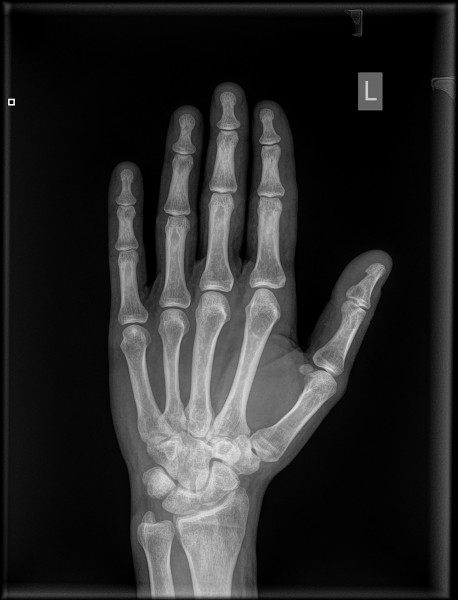

Uszkodziłem sobie palca wskazującego i jest nieco opuchnięty. Bardzo mocno wygiął mi się w górę, aż chrupnęło. Trochę boli mnie na wszystkich zgięciach. Wizytę u ortopedy mam za parę dni, a chciałbym się dowiedzieć, czy mam się czego obawiać. Załączam zdjęcia rtg wykonane dzisiaj.

IMG-0002-00001.jpg